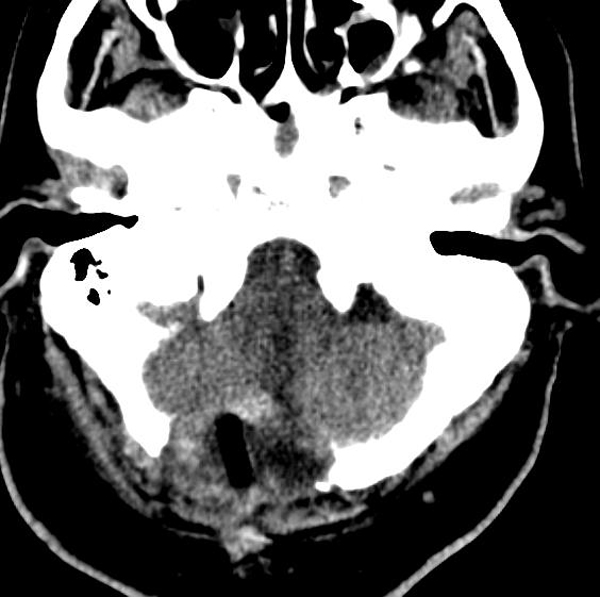

12月27日,陜西省核工業(yè)二一五醫(yī)院成功為一名73歲患者行延髓腫瘤切除術(shù),此次手術(shù)為咸陽(yáng)市首例,填補(bǔ)了咸陽(yáng)地區(qū)級(jí)醫(yī)院獨(dú)立開展腦干腫瘤切除的技術(shù)空白,標(biāo)志著二一五醫(yī)院在腦干病變的診療技術(shù)上再上新臺(tái)階。 73歲的劉...